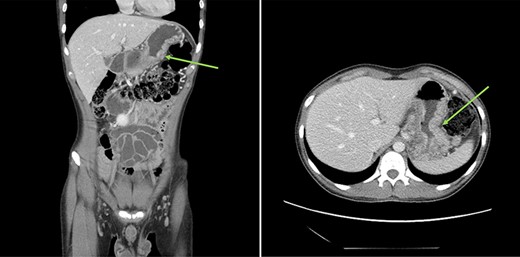

Urgent gastroscopy revealed a giant gastric ulcer in the antrum (Fig. 1) which was biopsied and sent for pathological investigation. The ulcer displayed no bleeding stigmata. He was started on eradication therapy for Helicobacter pylori. Pathology revealed a signet ring adenocarcinoma of the stomach (Fig. 2A and B). A computerized tomography (CT) scan (Fig. 3) showed a large mass in the distal stomach, and the ensuing positron emission tomography (PET) scan (Fig. 4) showed enlarged D1 perigastric lymph nodes with no obvious metastatic disease.

: (A and B) CT scans (coronal and axial views) showing a large mass in the distal stomach (green arrows).